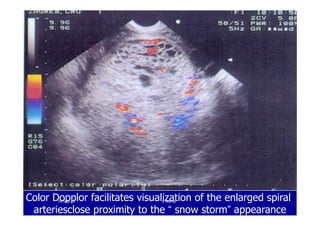

Color Dopplor facilitates visualization of the enlarged spiral

arteriesclose proximity to the “ snow storm” appearance